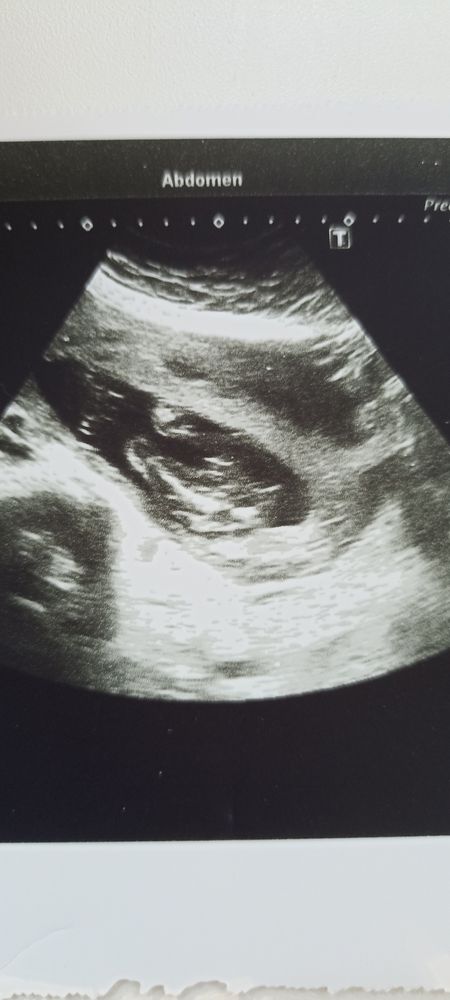

Кто тут прячется?Изображение Изображение

14.05.2025

Лина, похоже на мальчика

15.05.2025